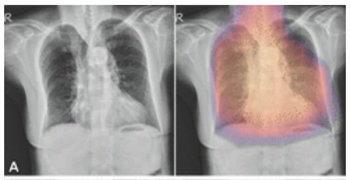

New research shows the use of adjunctive AI resulted in a 12 percent higher sensitivity rate for lung nodule detection in comparison to radiologists without AI.